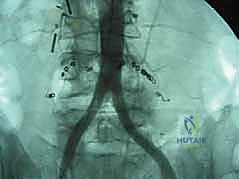

الخطوة 2: التعامل مع الأوعية الدموية (Vascular Mobilization)

هذه هي الخطوة الأكثر دقة. أمام العمود الفقري القطني توجد الأوعية الدموية الكبرى في الجسم (الشريان الأورطي والوريد الأجوف السفلي وتفرعاتهما). باستخدام أدوات دقيقة ورؤية مكبرة، يتم تحريك هذه الأوعية بلطف شديد لحمايتها وكشف القرص الفقري المستهدف (غالباً L4-L5 أو L5-S1).

الخطوة 5: التثبيت (Fixation)

لضمان أقصى درجات الثبات والسماح للعظم بالاندماج بمرور الوقت، يتم تثبيت القفص باستخدام شريحة معدنية صغيرة ومسامير من التيتانيوم تُثبت في الأجسام الفقرية من الأمام. في بعض الحالات، قد يرى الدكتور هطيف ضرورة إضافة تثبيت خلفي بمسامير عبر الجلد (Percutaneous Pedicle Screws) لزيادة الدعم.